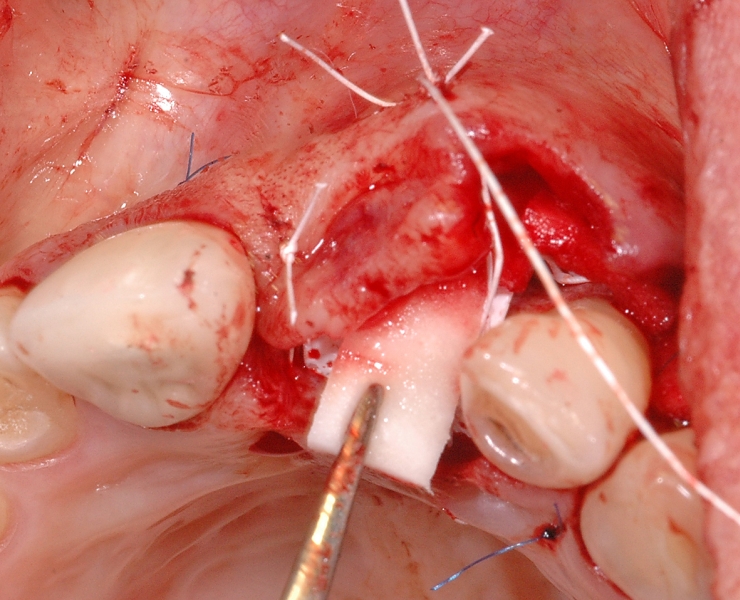

8/18 - Soft tissue thickening of the buccal side with mucoderm® and recession treatment of tooth 23GBR together with soft tissue augmentation with mucoderm® and maxresorb® - Dr. S. Scherg